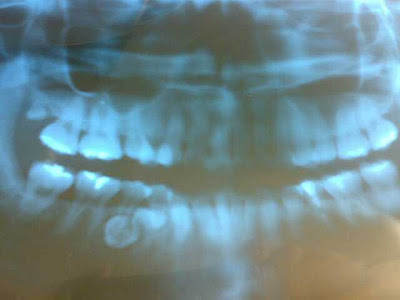

As I was saying, I had to take 4 x-rays, of which 2 are the inner teeth, one is of my jaw (the cool machine rotates around my head!!), and the last one I can't really remember, but the machine was also rotating around my jaw area.

Just to make the picture clearer.